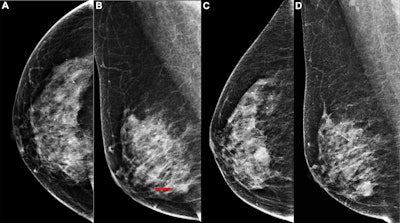

Images depict the right breast in a 63-year-old woman with interval breast cancer. (A, B) Screening mammograms in the (A) craniocaudal and (B) mediolateral oblique views show a right breast asymmetry (arrow) initially interpreted as normal tissue (BI-RADS category 2). (C, D) Diagnostic mammograms 17 months later in the (C) craniocaudal and (D) mediolateral oblique views reveal a high-density oval mass with indistinct margins. Ultrasound examination (not shown) demonstrated a 15.9 × 11.2 × 9.6 mm irregular hypoechoic mass, which was confirmed at biopsy to be invasive ductal carcinoma grade I.Images depict the right breast in a 63-year-old woman with interval breast cancer. (A, B) Screening mammograms in the (A) craniocaudal and (B) mediolateral oblique views show a right breast asymmetry (arrow) initially interpreted as normal tissue (BI-RADS category 2). (C, D) Diagnostic mammograms 17 months later in the (C) craniocaudal and (D) mediolateral oblique views reveal a high-density oval mass with indistinct margins. Ultrasound examination (not shown) demonstrated a 15.9 × 11.2 × 9.6 mm irregular hypoechoic mass, which was confirmed at biopsy to be invasive ductal carcinoma grade I.RSNA